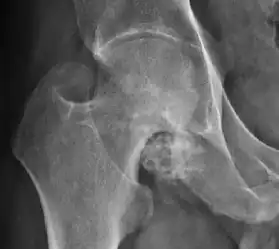

There are other pathological conditions that can affect the hip joint and radiographs help to make the appropriate diagnosis. Acute bacterial septic arthritis can be diagnosed by radiographs when a fast regional osteoporosis and destructive monoarticular process develops (Figure 1(f)). In case of tuberculous or brucella arthritis it is manifested as a slow progressive process, and diagnosis may be delayed.[1]

Synovial chondromatosis can be confidently diagnosed by X-ray when calcified cartilaginous chondromas are seen. However, other synovial proliferative processes, such as pigmented villonodular synovitis, require MRI for accurate diagnosis, although noncalcified synovitis can be suspected in radiographs by indirect signs, such as soft tissue swelling and/or erosions in the femoral head, femoral neck, or acetabulum (Figure 7).[1]

Figure 7:

-

Axial CT image of pigmented villonodular synovitis eroding the posterior cortex of the femoral neck.[1] -

Sagittal T2* gradient echo image showing a posterior soft tissue mass with hypointense areas secondary to hemosiderin deposition.[1] -

X-ray of synovial chondromatosis.[1] -

CT of synovial chondromatosis.[1]